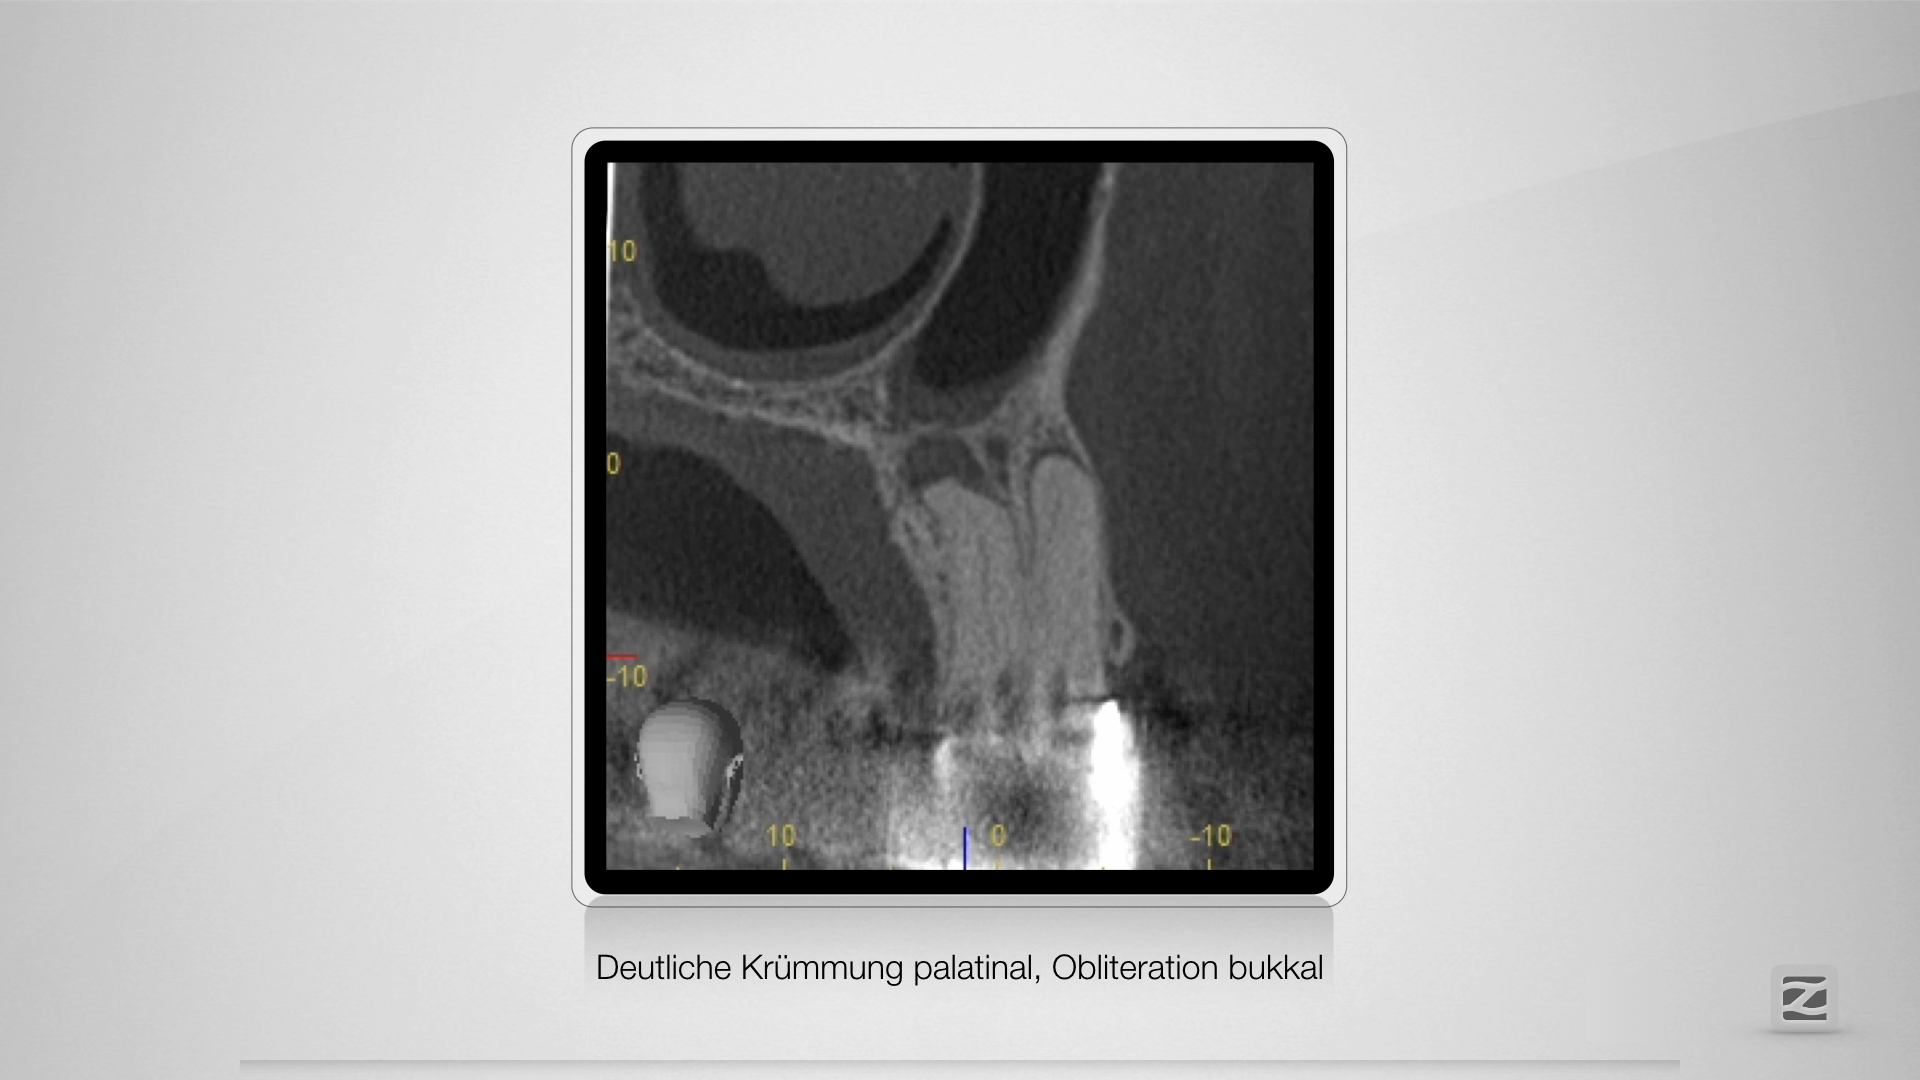

Dummheit gehört bestraft.